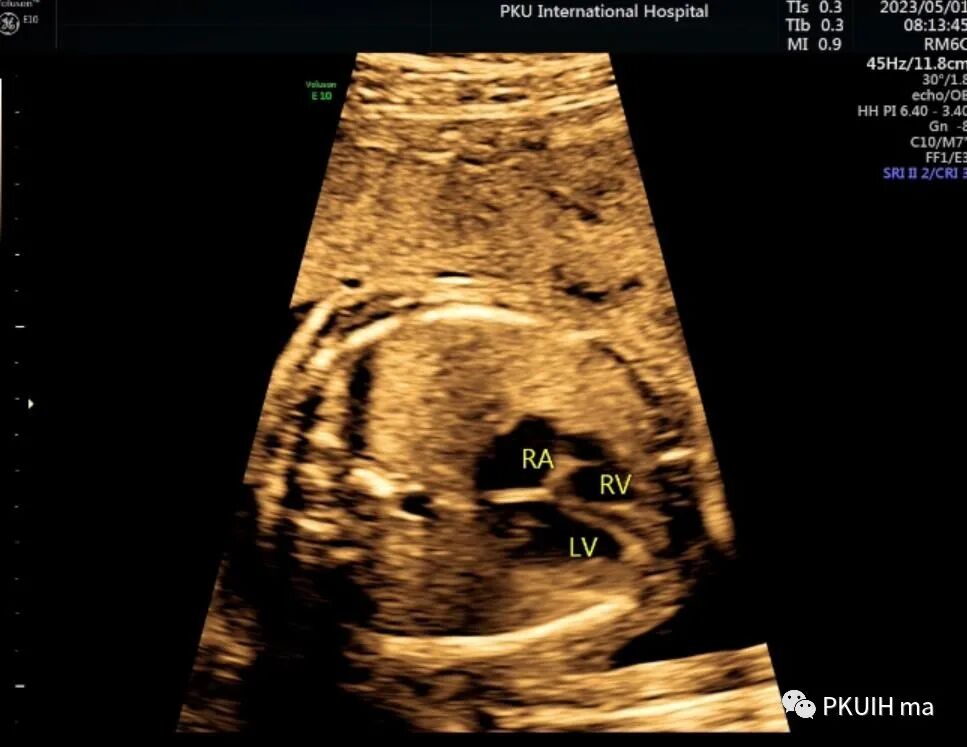

今天跟大家分享一例镜面人的超声图像。患者22周常规系统排畸未提示异常,本次24周+行胎儿心脏超声检查发现内脏反位。图像如下

胎儿头位(右枕横位),胎儿小脑半球和脊柱均在右侧,采用右手法则判断近场为胎儿的左侧远场胎儿的右侧

胎儿胃泡位于右侧,肝脏和胆囊位于左侧,主动脉位于脊柱右前方,下腔静脉位于脊柱左前方

胎儿心脏大部分位于右侧,心尖指向右前方,左房位于脊柱前方,右室位于胸骨后方,右室心尖部可见调节束,心室–大动脉连接关系正常,整个心脏呈镜面右位心。